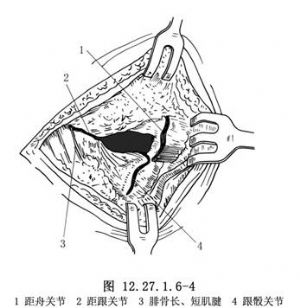

5.2.7.3 3.显露跟骰及距舟关节

将伸趾短肌在跟骨前外附丽处切开,向远侧翻开,注意尽量保持其完整和血液循环,以便缝合时覆盖死腔及骨面。切开跟骰关节囊以显露跟骰关节,剥离距骨颈上外部的骨膜,切开距舟关节囊以显露距舟关节(图12.27.1.6-4)。

5.2.7.4 4.切除关节面、纠正畸形

用大切骨刀切除跟骨和距骨关节面,根据畸形的性质与程度,切除适量的楔形骨质。如为内翻畸形,应切除以外侧为基底的楔形骨质;反之如为外翻畸形,则应切除以内侧为基底的楔形骨质(图12.27.1.6-5A)。用切骨刀横行切除跟骰关节面,如有足前部内收,应切除以外侧为基底的楔形骨质;如为外展畸形,则应切除以内侧为基底的楔形骨质(图12.27.1.6-5B)。切除距舟关节面,如有高足弓,应切除以背侧为基底的楔形骨质。如显露困难,宜在内侧做一纵行辅助切口。切骨后观察足部畸形矫正情况,适当修整骨面,使三处骨面有良好接触,以便完全矫正畸形,并有利于骨愈合(图12.27.1.6-5C)。保留取下的骨质,去除软骨部分,作为松质骨植骨,植于各关节周围,要特别注意在距舟关节部位多植些碎骨,防止形成假关节。